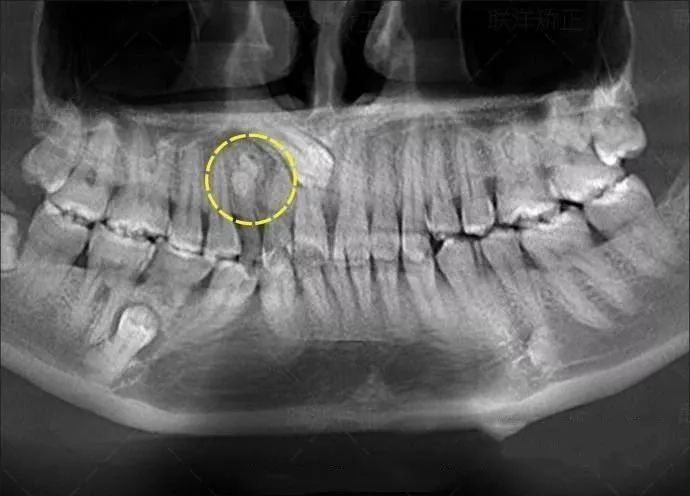

牙齿的牙根是埋在牙槽骨中的,医生没有透视眼,为了解患牙的牙根的形态、走向、长度及根尖周有无病变及病变大小,或者怀疑有肉眼无法确认的其它牙科问题,都会建议患者去牙科的X光,甚至,口腔CT来全面性地确认问题,以订定合适的治疗计划。